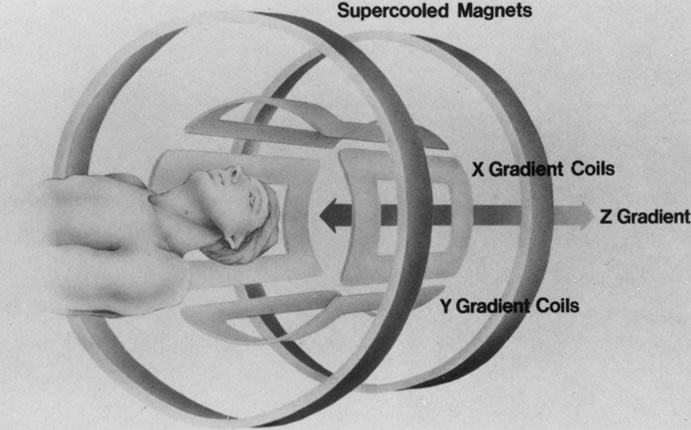

GRADIENT COILS

The spatial encoding information required for imaging the MR signal is achieved by use of gradient coils. These coils surround the patient's body in the MRI unit and select the plane (axial, coronal, sagittal, or oblique) to be studied (Fig. 6). A gradient magnetic field is applied by these coils perpendicular to the specified tissue section and isolates the desired plane's RF signal. These signals are further localized by additional manipulation of the magnetic fields parallel to the tissue section into multiple-volume units called voxels (Fig. 7). Each voxel represents a group of hydrogen nuclei with a unique sum of frequencies and phases. A computer reconstructs the signals from these individual three-dimensional voxels into corresponding pixels that compose the two-dimensional image of that plane. The intensity, or whiteness, of each pixel is proportional to the strength of the RF energy obtained from the corresponding voxel.5,15